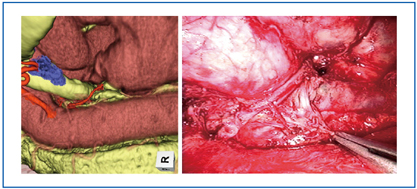

![]() 図5 シミュレーション画像(左)は術中所見(右)をきわめて良好に反映している。 |